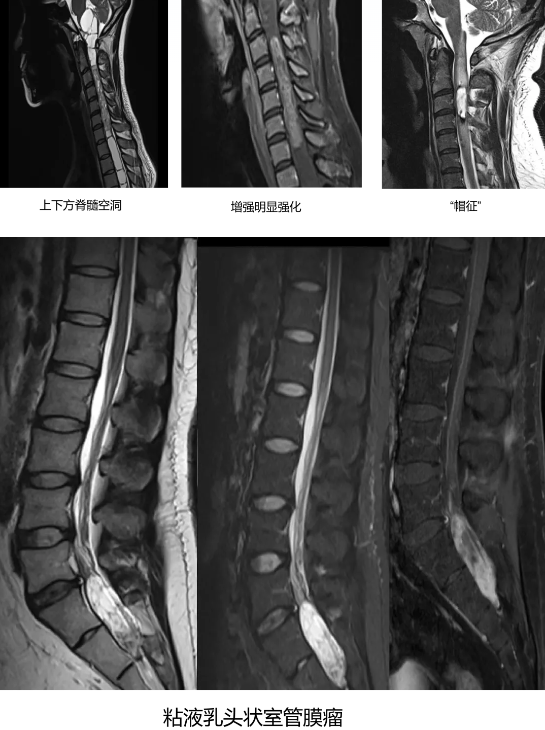

特殊亚型:粘液乳头状室管膜瘤 [3, 4]

部位: 几乎全部位于圆锥、终丝或马尾。

形态: 常呈分叶状,可因出血、囊变而信号混杂。

强化: 显著不均匀强化,有时因粘液聚集和出血,呈现「茄子」或「葡萄串」样外观。

特征: 易导致邻近骨质侵蚀。

1. 部位与形态: 位于髓内,常呈边界清晰的梭形或腊肠形肿块。肿瘤常位于脊髓中央,可对称性或轻度偏心性生长。约 20-50% 的病例,肿瘤头端和/或尾端可出现囊变,这些囊腔通常为非肿瘤性的脊髓软化或空洞。

「帽征」: 在肿瘤两极的 T2WI 上常见低信号「帽」,为含铁血黄素沉积,源于肿瘤易出血的特性。